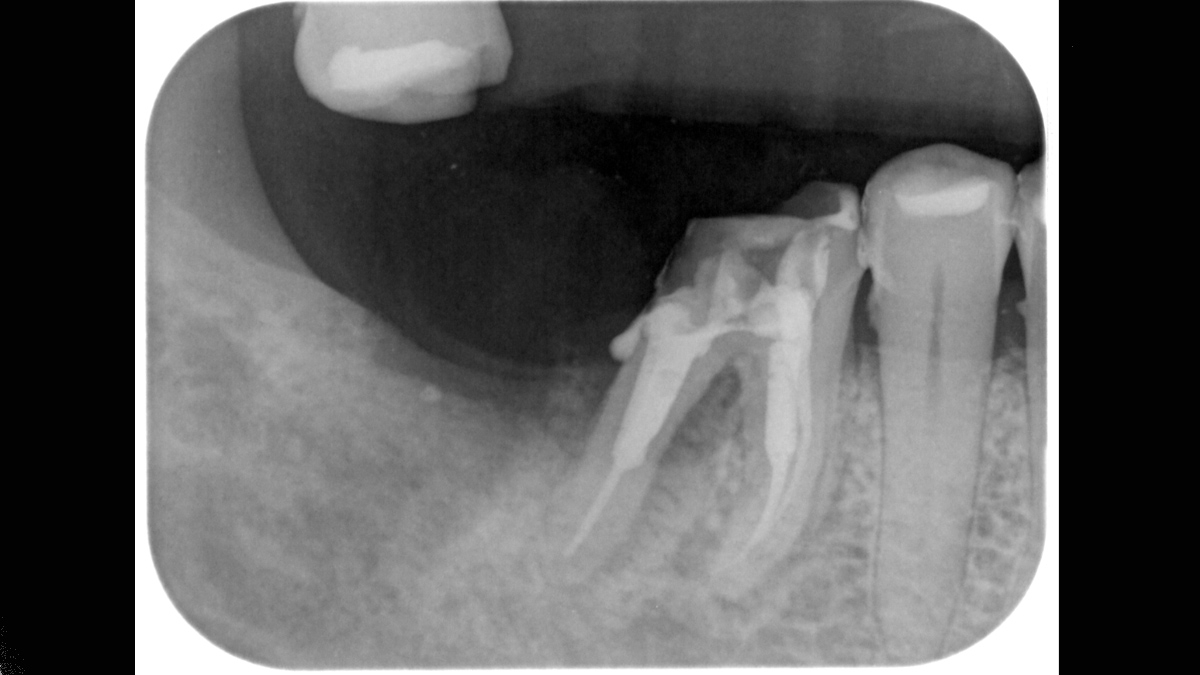

Xios Scan provides a gentle, easy introduction into the world of digital X-ray imaging. If you want to switch from film to digital without having to give up your tried-and-true working methods, imaging plate technology offers you a myriad of possibilities. You can experience many of the advantages of digital imaging without a darkroom and chemicals while your team continues its regular workflow.

The Xios Scan integrates seamlessly with the Dentsply Sirona X-ray units and software to deliver better, safer and faster intraoral diagnostics.